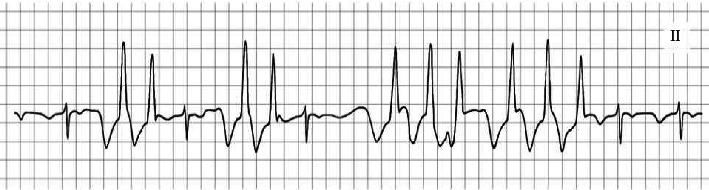

背景:一名全麻患者体位改变后发生暂时性心律失常的新病例报告强调了由于患者体位改变时外周插入的中心静脉导管([CVC] PICC)尖端尾侧运动可能导致潜在致命性心律失常的可能性。病例介绍:我们报告了一个44岁的女性患者在全身麻醉下进行腹腔镜肾上腺切除术,在体位改变后发生的暂时性心律失常。患者术前使用心电图(ECG)引导的针尖确认系统(TCS)插入PICC。结论:本病例报告讨论了全麻下最佳TCS,强调警惕心电监测,提出了预防全麻下心律失常的措施。

Background: The novel case report of a temporary arrhythmia that developed after a positional change in a patient under general anesthesia emphasizes the possibility of potentially lethal cardiac arrhythmias that may develop owing to caudal movement of the peripherally inserted central venous catheter ([CVC] PICC) tip when changing patient positions. Case Presentation: We present a case of temporary arrhythmia that developed after a positional change in a 44-year-old female patient scheduled for laparoscopic adrenalectomy under general anesthesia. She had undergone preoperative insertion of a PICC using an electrocardiogram (ECG)-guided tip confirmation system (TCS). Conclusion: The case report discusses the optimal TCS and emphasizes vigilant ECG monitoring, suggesting measures to prevent these arrhythmias under general anesthesia.